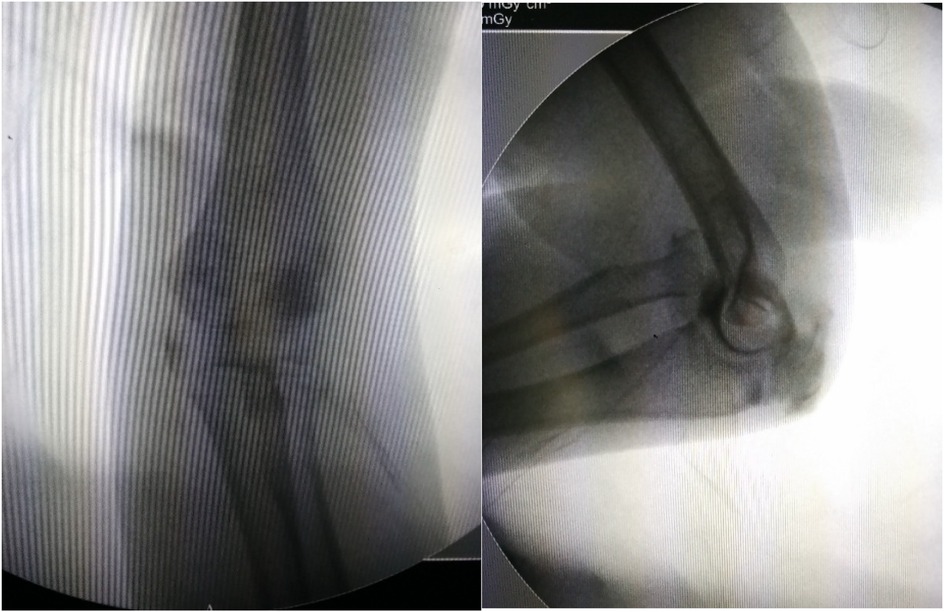

Objective: To investigate and analyze the application value of elbow arthrography in the treatment of chronic radial head dislocation in children. Methods: From January 2014 to January 2017, 15 children with chronic anterior radial head dislocation were treated (11 boys, 4 girls; average age 9 years, range 3-11 years). Intraoperative elbow arthrography was performed to assess the position of the radial head relative to the joint capsule. The nature of the dislocation was confirmed by opening the joint capsule to directly observe the relationship between the radial head and capitellum, as well as the morphology of the radial head. Reduction of the radial head was achieved via proximal ulnar osteotomy, and fixation was performed using a plate and screws with or without Kirschner wires (K-wires). Results: Elbow arthrography showed the radial head was located within the joint capsule in 12 cases and outside the capsule in 3 cases. Among the cases: All 8 congenital dislocations had the radial head within the joint capsule. Of the 7 traumatic dislocations, 4 had the radial head within the capsule and 3 outside. Direct inspection after capsulotomy confirmed the arthrography findings and revealed characteristic morphological differences. In congenital dislocations, there was no scar tissue between the radial head and capitellum, and the radial head fovea was shallow and flat. In traumatic dislocations, obvious scar tissue was present between the radial head and capitellum, and the radial head fovea was distinct. Follow-up ranged from 9 months to 4 years (average 2 years 5 months). Postoperative radiographs showed no cases of radial head re-dislocation or subluxation. Postoperative elbow range of motion improved in all patients, with no reports of pain or functional instability. Conclusion: Elbow arthrography serves as a valuable adjunct for differentiating between congenital and traumatic radial head dislocations, thereby informing both surgical strategy and the decision for supplemental fixation. When stable bony alignment is achieved, proximal ulnar osteotomy without annular ligament reconstruction represents an effective management strategy for chronic radial head dislocation in children.